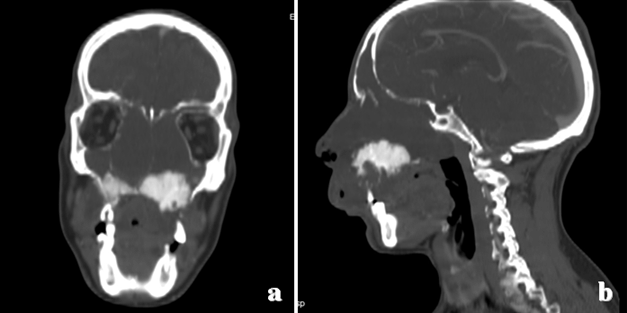

Cursor on image to zoom/Click text to open image

Figure 2: Computed tomography scan after injection of contrast medium. (a) Coronal and (b) Sagittal images demonstrate the lesion originating in the left upper quadrant of the maxilla and invading the nasal cavity and the sphenoidal and frontal sinuses.